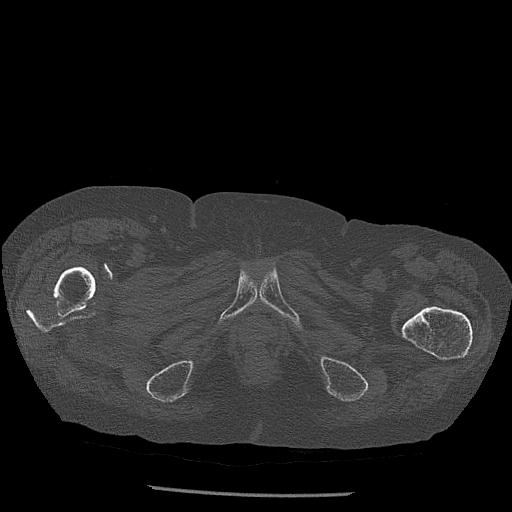

91983 11/16 左膝 2R 11/18 2R 55歳男性 脛骨骨切り術